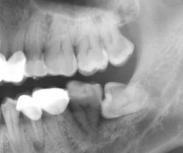

口腔粘膜病是指除腫瘤以外,發生在口腔粘膜和軟組織的疾病。口腔粘膜病病種較多,患病率較低,病損多種多樣,病因復雜,有些病與全身因素關系密切,在診治過程中要有整體觀念。口腔某一部位粘膜的正常色澤、外形、完整性與功能等發生改變的疾病。病變種類繁多,可以組合成復雜多樣的損害。有些全身性疾病也在口腔粘膜上有所表現,而有些口腔表征可作為全身疾病診斷的依據或線索。

- 常見癥狀:口舌潰爛、舌體干裂、聲音嘶啞 、口干口苦、口腔扁平苔癬、口腔炎、導致飲食困難、口腔疼痛難忍、反復發作